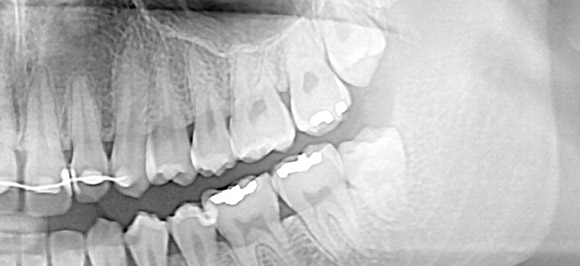

사랑니발치

18세 전·후로 자라는 사랑니, 이름과 달리 대부분은 골칫덩이로 자라…

혹시나 기형 혹은 잇몸 안에서 자라는 매복이라면?

주변은 물론 구강 전체 악영향을 줄 수 있어, 발치가 필요!

(매복)사랑니 발치! 이런 환자분들은 필요합니다.